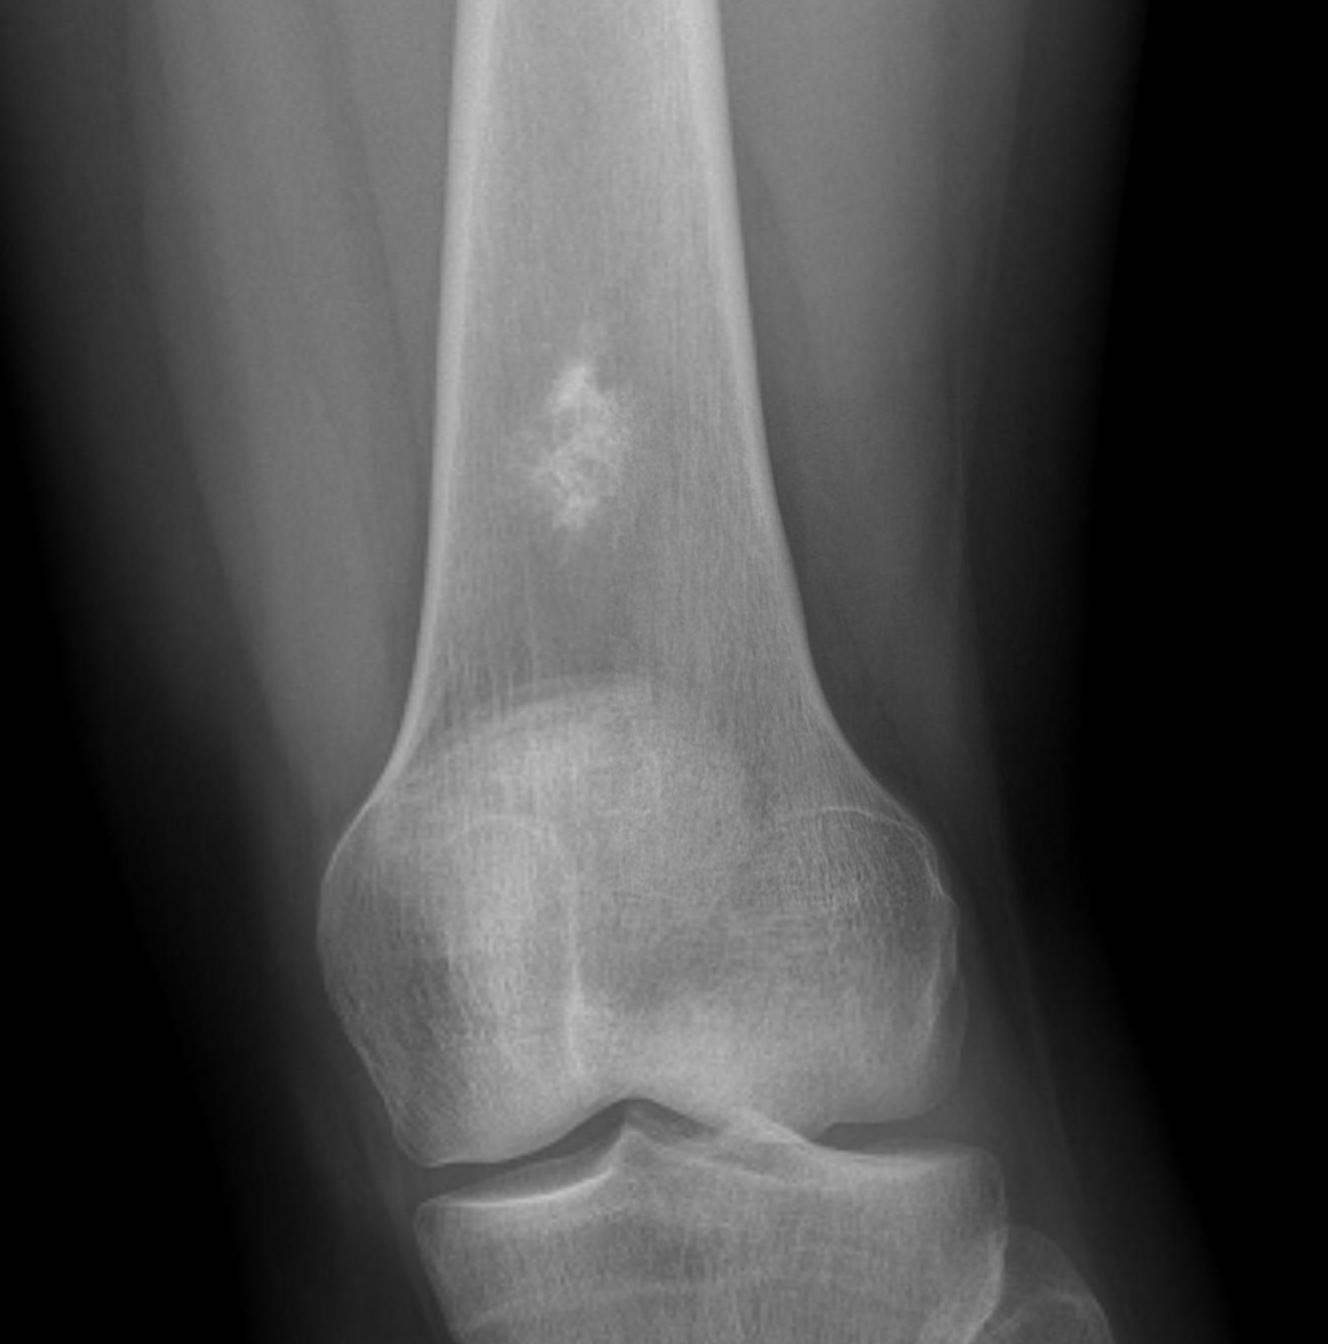

X-ray

Intralesional calcification - punctate, stippled calcification and broken rings

Differential diagnosis long bone with intralesional calcification

1. Enchondroma

2. Bone infarct

3. Chondrosarcoma